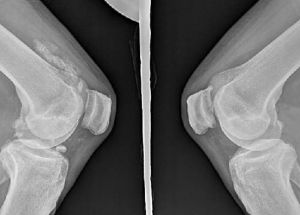

1、X線光片 滑膜骨軟骨瘤病的X線變現不同,典型表現為受累關節遍布多個大小不一的鈣化或骨化的游離體,呈環形或點彩狀,界限清楚,關節腔變窄、骨質侵蝕和骨質疏鬆很少見。表現不典型這可出現骨質侵蝕、軟骨下囊腫、偶見關節間隙變窄、關節半脫位等。2、其他影像檢查技術關節造影、CT或MRI檢查可顯示鈣化或骨化的游離體位於關節腔內,也可呈線狀聚集於滑膜上。